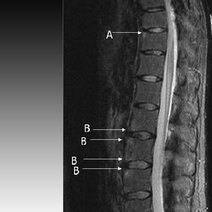

- 强直性脊柱炎(AS)是以骶髂关节和脊柱附着点炎症为主要症状的疾病。与HLA-B27呈强关联。某些微生物(如克雷白杆菌)与易感者自身组织具有共同抗原,可引发异常免疫应答。是四肢大关节